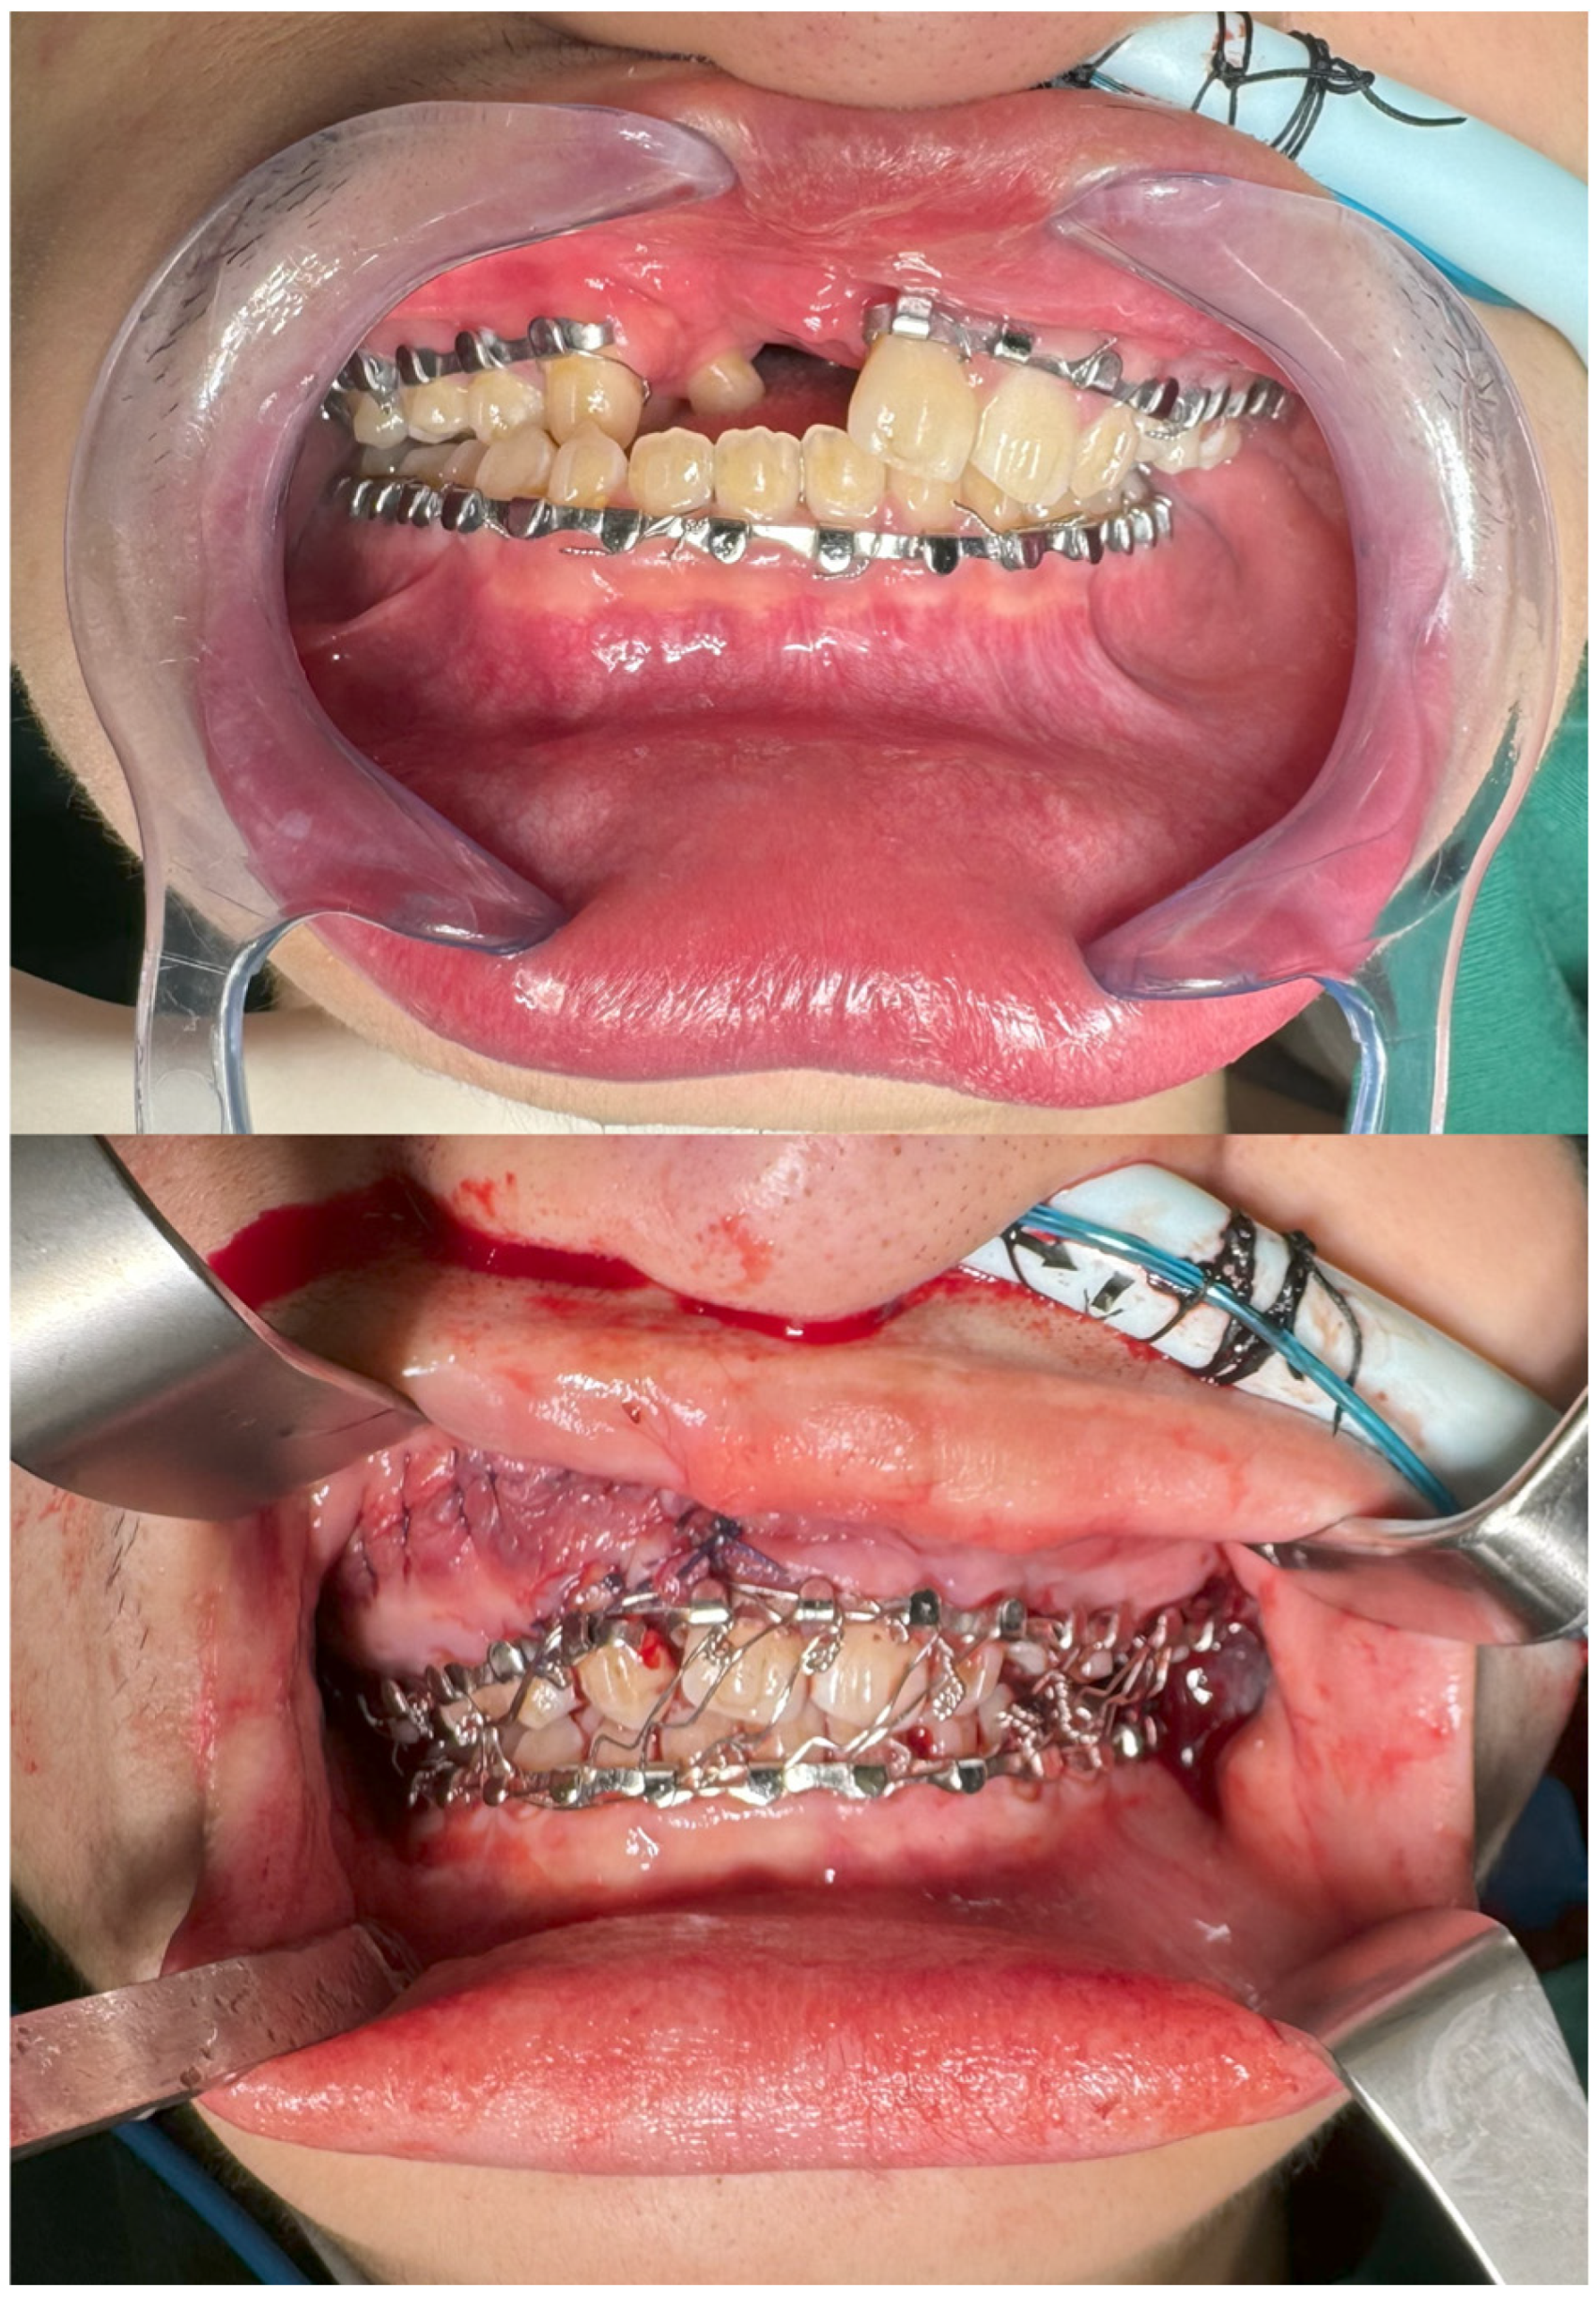

2. Materials and Methods

2.1. Preoperative Planning

2.2. Intra-Operative Navigation